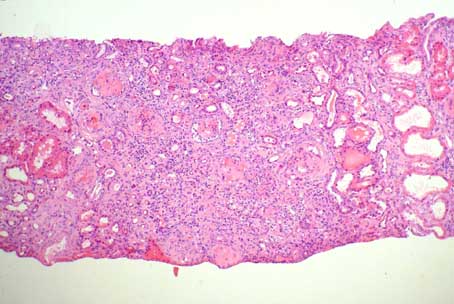

Se toma biopsia renal. Observe las imágenes.

Figura 1.

(H&E, X100)